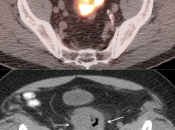

Presentation of Primary Cancer:

- Focal bowel uptake, usually with associated bowel wall thickening.

- If long-segment, think inflammation.

- If diffuse, usually normal physiologic uptake.

- Normal physiologic bowel uptake (discussed here) can be very focal and isolated to only one part of the colon, most commonly the cecum and rectum. Always look for associated bowel wall thickening on the CT images.

- Benign polyps (discussed here) can be intensely avid. They are usually not visible on the CT images.